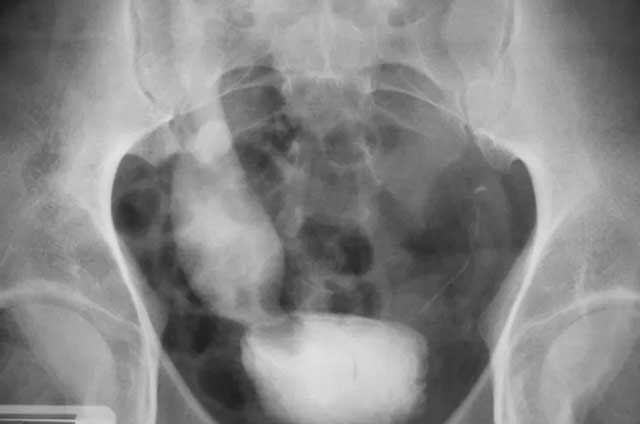

Los síntomas más comunes cuando una persona empieza a padecer cáncer de la vejiga son el dolor y la obstrucción urinaria (dificultad para orinar). Cuando se presentan estos síntomas, el paciente deberá hacerse una cistoscopia, para inspeccionar el interior de la vejiga y de la uretra. De esta forma se pueden detectar irregularidades e iniciar un tratamiento.